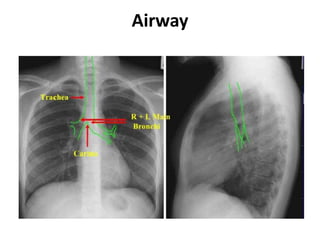

Airway